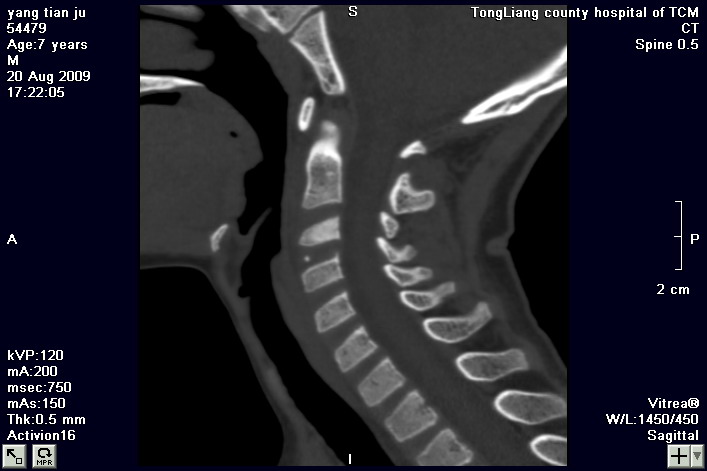

标题: PED2853:颈3/4椎间盘内高密度钙化灶,请各位会诊. [打印本页]

标题: PED2853:颈3/4椎间盘内高密度钙化灶,请各位会诊.

患儿,7岁,颈部疼痛3天,颈部活动受限.

本例应该是典型的儿童钙化性椎间盘病。

儿童钙化性椎间盘病发病年龄多在5~12岁,男女比例相当,大多数患儿发病主要表现为颈部疼痛,伴活动受限。少数有吞咽不适或肢体瘫痪。有一部分患儿无症状,是在其它检查时发现。病因尚不完全明了,可能的有:1、感染。2外伤。

儿童颈椎椎间盘钙化系一良性自限性疾病,可见于颈、胸、腰椎,以颈椎为多发,腰椎少见,多为单发。钙化位于髓核,也可累及软骨板和纤维环引起钙化主要发生于c 4~7  的髓核位于椎间隙正中或偏后,少数向前疝出,以后部多见,呈梭状、盘状、团块状或半环状;(2)颈椎生理曲度变直,椎间隙正常或增宽;(3)相邻椎体可变扁,局部凹陷变形,椎体前下缘鸟嘴状增生,或呈钳口状改变,椎前软组织增厚及环枢椎半脱位;(4)ct可清晰显示椎间盘髓核 位置的钙化灶及经破裂的纤维环向椎管内突出。(5)mri,钙化在t1及t2加权像上均呈低信号,并可见脊髓组织内异常信号。